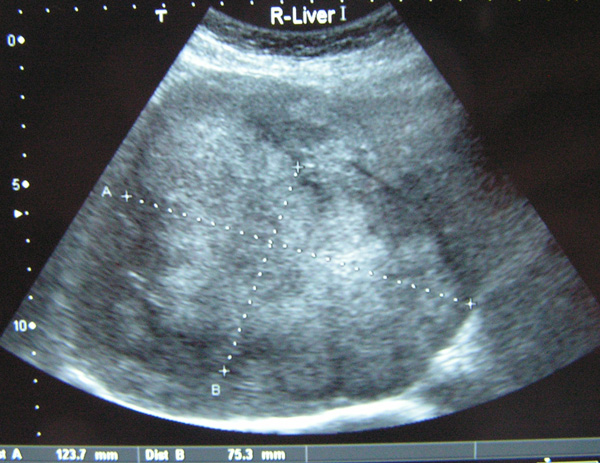

A CT scan in May 2014 showed more nodules in her liver (pictures below). The cancer had also spread to her bone. Amy received bonefos injection for her bone metastasis.